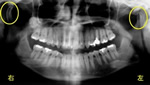

まず下記のAさんのレントゲン写真を見てみましょう。

レントゲンの黄色い◯部分が顎関節です。

左右の黄色い部分の骨の形、大きさの違いが分ると思います。

左に比べて右が細くなっています。

人間の身体はだいたい、左右対称にできています。

両手足をみても左右対称ですよね。

顎関節も正常な方は左右の長さ、形がだいたい同じです。

では、なぜこのように左右が違ってくるのでしょう。

この患者さまに対する院長、吉本の診断は次の通りです。

「噛み合わせ(咬み合わせ)」と「右上奥歯ぐきの中に埋まっている親知らず」